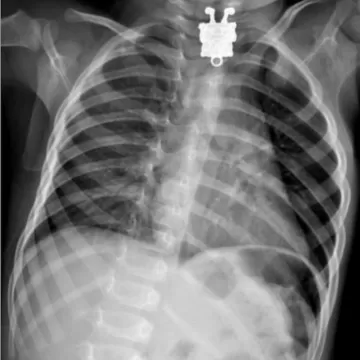

Но поскольку эндоскопия может быть недоступна (нет дежурного эндоскописта в небольшой больнице и т. д.), для диагностики инородного тела может использоваться рентгенограмма области шеи и грудной клетки в двух проекциях. Если инородное тело рентгенонеконтрастно (пластик, гидрогелевый шарик и т. п.), рентгенограмму делают с контрастом. Пациенту предлагают выпить непрозрачную для рентгеновских лучей бариевую взвесь, на фоне которой становится видно инородное тело.